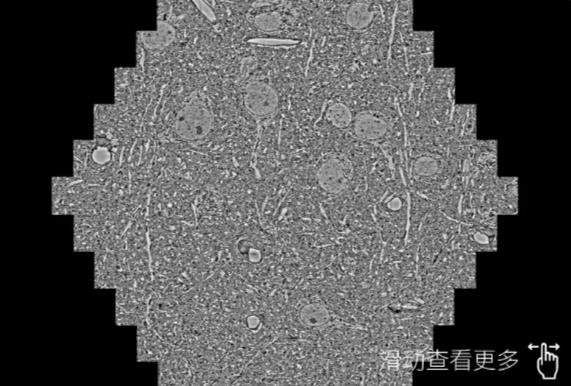

鼠脑切片。左图使用连云港蔡司连云港扫描电镜MultiSEM706对165μmx143pm面积区域成像,耗时仅需1.5秒。右图为鼠脑切片中30μm区域放大效果。样品由芝加哥大学B.Kasthuri提供。